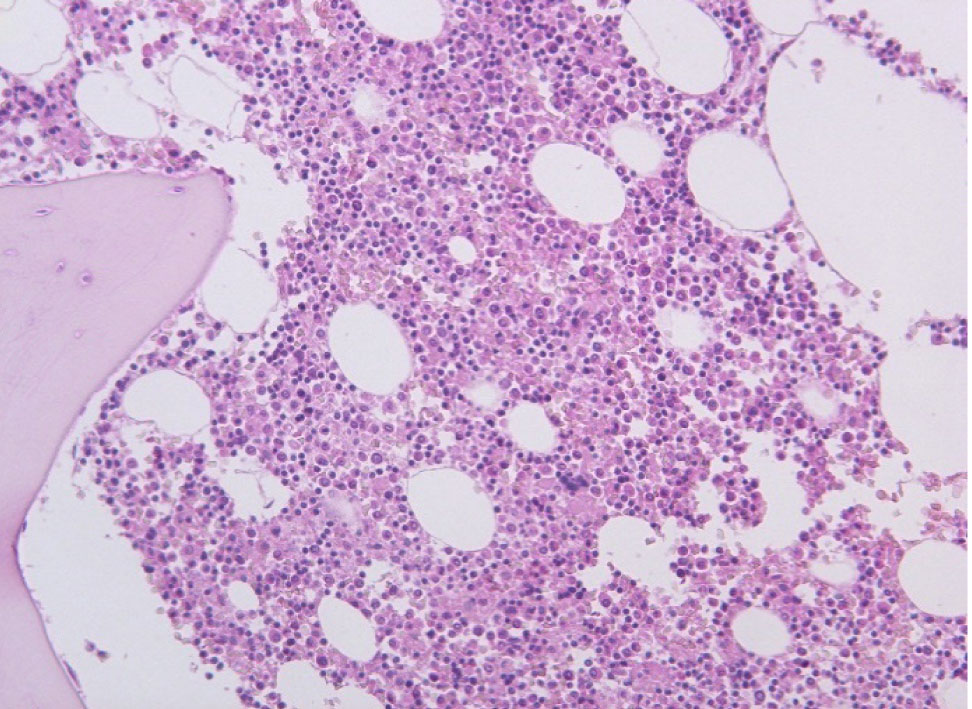

При исследовании ткани легких в стенке сосудов видны плотные гомогенные массы, дающие положительную реакцию на амилоид. При исследовании органов в поляризационном микроскопе обнаружено зеленоватое свечение амилоида. В костном мозге скопление клеток, дающих положительную реакцию с моноклональными антителами к CD38 (рис. 5, 6).

Рис. 5. Пролиферация клеток костного мозга. Окраска гематоксилин-эозин, ×200

Рис. 6. Экспрессия CD38 в плазматических клетках костного мозга, ×200

Патологоанатомический диагноз: Первичный амилоидоз c поражением почек, селезенки, миокарда, легких. Уремия. Водянка серозных полостей.

Таким образом, у больного был амилоидоз с поражением почек, селезенки, сердца и легких. Обнаружение в костном мозге пролиферации лимфоцитов, дающих реакцию с моноклональными антителами к CD38, дает основание предполагать развитие первичного амилоидоза, который связан с гиперпродукцией легких цепей иммуноглобулина с последующим образованием в тканях внутренних органов AL-амилоида.